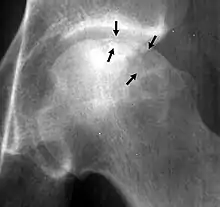

A radiograph of a left hip joint, which reveals a thin, curvilinear lucent line parallel to the cortical margin of the femoral head, in a patient with avascular necrosis.

In radiology, the crescent sign is a finding on conventional radiographs that is associated with avascular necrosis.[1][2][3] It usually occurs later in the disease, in stage III of the four-stage Ficat classification system.[1] It appears as a curved subchondral radiolucent line that is often found on the proximal femoral or humeral head.[1] Usually, this sign indicates a high likelihood of collapse of the affected bone.[1] The crescent sign may be best seen in an abducted (frog-legged) position.[1][4]